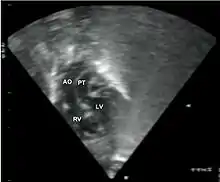

Additional images